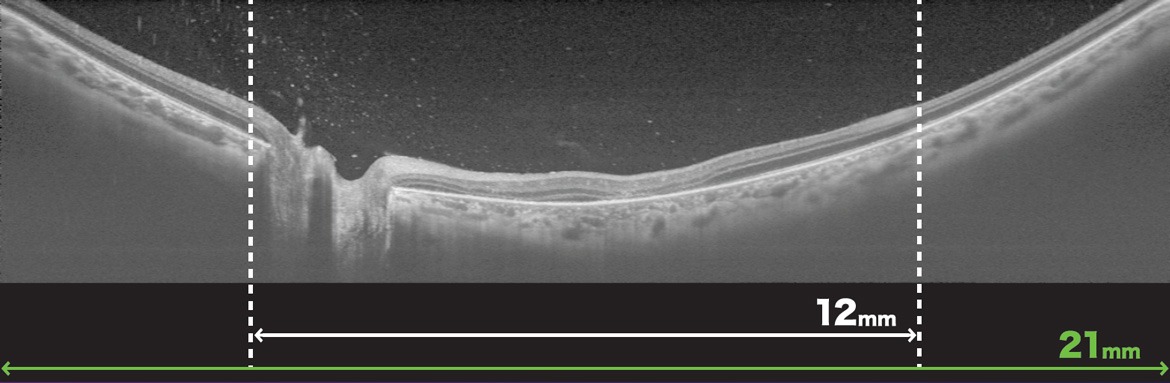

- Wide-Field OCT Max. 21mm Scan

The 12x9mm wide-field scan covers the optic nerve and macula and can be captured in one acquisiton to provide a comprehensive assessment of the posterior pole with reference database comparison.